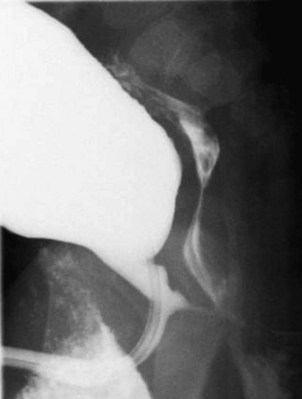

Anterior urethral obstruction is rare compared with posterior urethral valves. Although these obstructive structures may be called valves, they often occur in the form of a diverticulum of the urethra with one wall acting as an obstructive “valve” (Fig. 126–13) (Tank, 1987). There are also some reported cases of urethral flaps or valves in the anterior urethra (DeCastro et al, 1987; Scherz et al, 1987). The first case was reported in 1906, and the total number in the literature is small (Watts, 1906; Williams and Retik, 1969; Firlit et al, 1978).

Figure 126–13 A, Voiding cystourethrogram shows a severe case of anterior urethral valves. The bladder is almost empty, and there is massive reflux. The valve is in the form of a diverticulum. B, The filled diverticulum can sometimes be seen as a mass on the penis that resolves between voids. Pressing on the mass may express urine for some time after voiding.

Anterior urethral diverticuli typically occur where there is a defect of the corpus spongiosum, leaving a thin-walled urethra (Fig. 126–14). This segment of urethra balloons during voiding and causes a mass that is sometimes visible along the ventral wall of the penis. The mass resolves as urine drains from it between voids, and when full, urine can be expressed from the diverticulum by applying pressure. The distal edge of the diverticulum forms a flap that obstructs the flow of urine, and the effects of anterior urethral valves can be as damaging to the urinary tract as those of the posterior urethra. The embryology of these structures remains unclear but seems to be unrelated to the development of posterior urethral valves.

Figure 126–14 Voiding cystourethrogram demonstrates an anterior urethral diverticulum trapping urine during voiding.

Boys with anterior urethral valves often present later in childhood with infection, straining to void, or incontinence. One third present with voiding symptoms, a third with antenatal hydronephrosis, and the remainder with a visible diverticulum (Van Savage et al, 1997). The degree of obstruction can be severe and produce pressures as high as with the posterior urethral valve. Spontaneous rupture of the fetal bladder in anterior urethral valves has been reported (Merrot et al, 2003).

Diagnosis depends on VCUG or cystoscopy. It may be difficult to pass a catheter into the bladder because the catheter often easily enters the diverticulum and becomes trapped. Treatment is similar to that of posterior urethral valves in that relief of obstruction is the most important goal. In severely ill children or young infants a vesicostomy is a good option for temporary drainage, allowing the urinary tract to decompress and delaying urethral repair until conditions are optimal (Rushton et al, 1987).